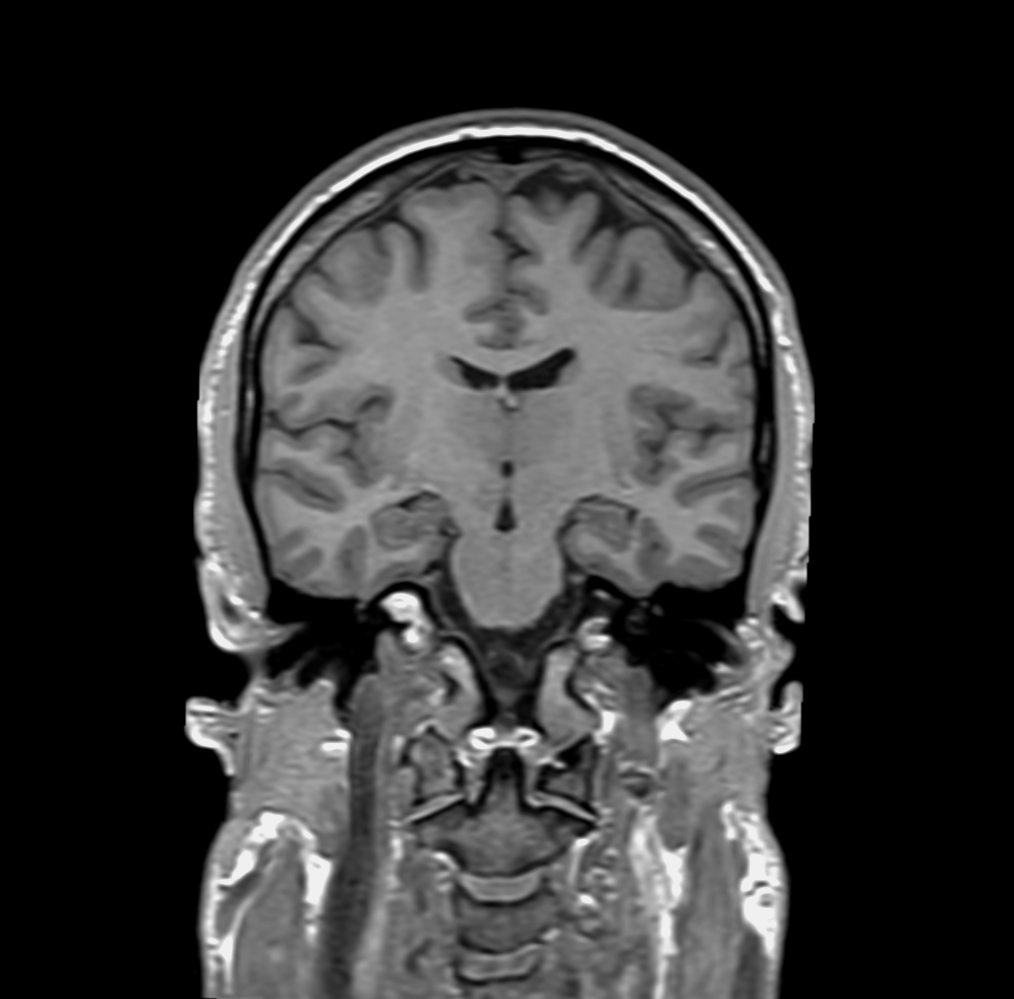

Coronal T1w IR

T1w 3D FFE (coronal reformat)